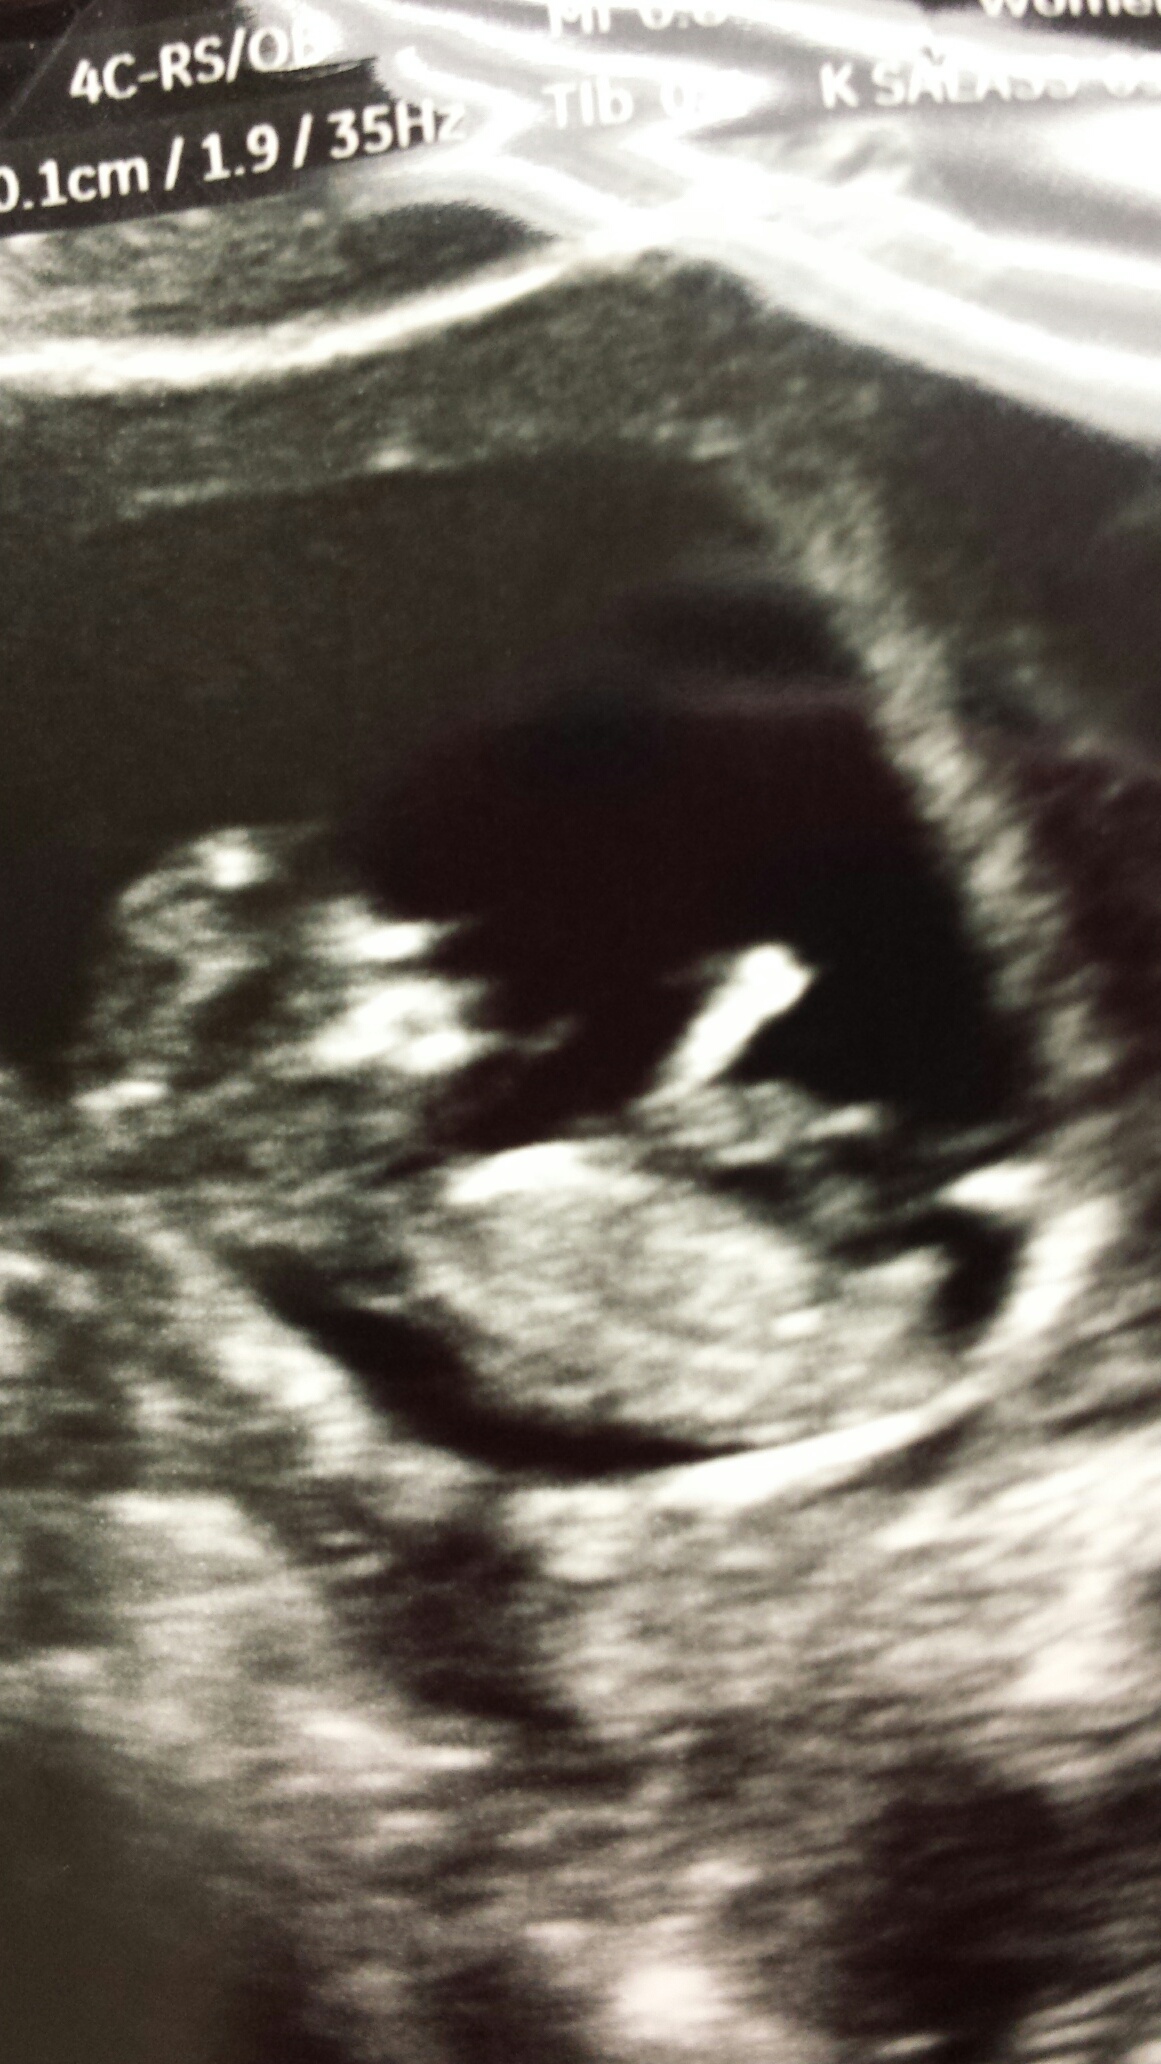

I'm gonna guess boy. But baby is not in an ideal position in either pic (curled back, sitting upright). So it's a tentative guess :)

Im confused by the thickness of the top "nub" like it could be leg or something.

Not sure as spine is bent. If laid flat possibly straight nub??? Mayb girl x

I'm wondering about the spine too as that nub is quite long?!

That is a BIG nub I would be very hesitant but agree likely a boy, but the chin is pointy and skull looks like my daughters. Hope you get your gender desire x